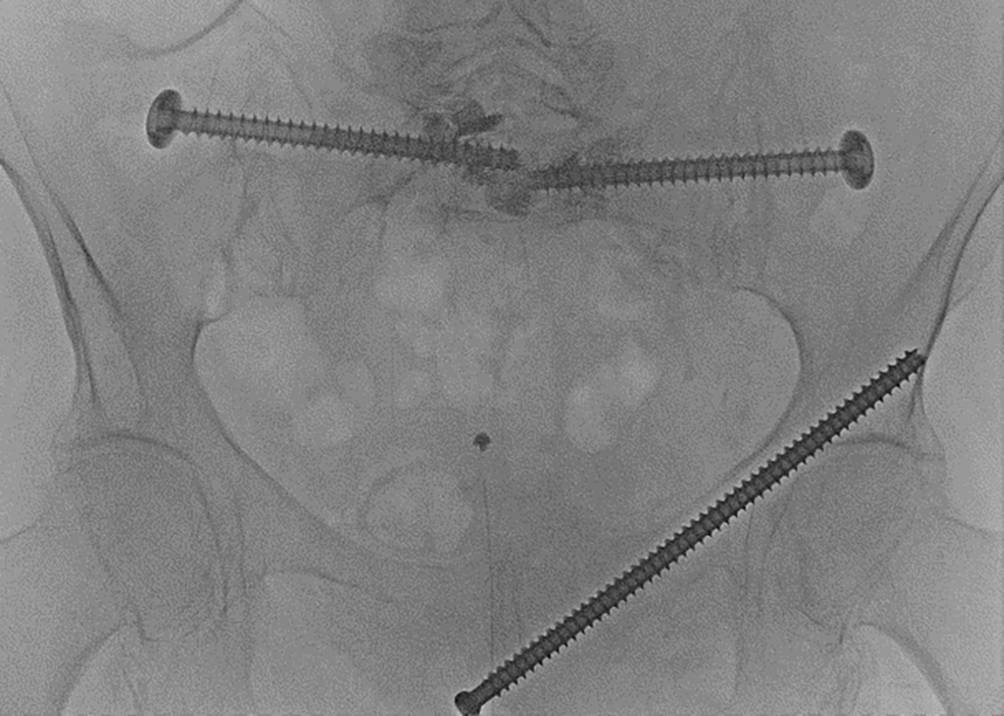

Fig. 11

An overview of the pelvis showcasing the final results. All incisions are irrigated and closed by suture